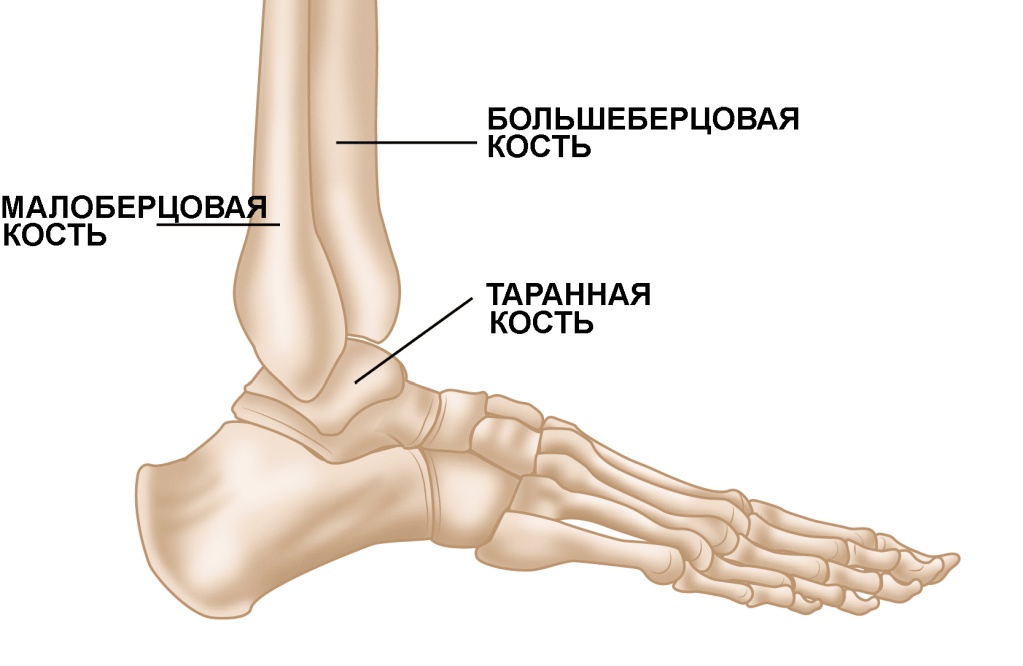

Анатомические фото голеностопного сустава и его суставных поверхностей